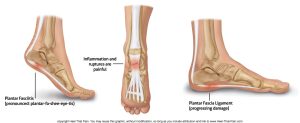

Plantar fasciitis is the inflammation or irritation of the plantar fascia, a strong band of tissue that runs along the bottom of your foot—from your heel to your toes. This tissue acts as a shock absorber and supports the arch of your foot. When it becomes overstressed or damaged, it leads to sharp, persistent pain that can disrupt your daily routine.

Individuals with very **high arches** or **flat feet** are more prone to plantar fasciitis because their natural foot mechanics place added pressure on the fascia.